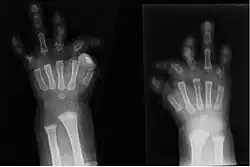

Brachydactylie

La brachydactylie est un terme de médecine signifiant : brièveté d'un ou de plusieurs doigts. C'est une caractéristique dont la transmission génétique est généralement autosomique dominante[1],[2]. Il existe cinq types de brachydactylie de A à E et cinq sous types de A1 à A5.

La brachydactylie de type D est caractérisée par un pouce court et arrondi avec un ongle large. Elle est causée par une phalange distale courte d'un ou des deux pouces. C'est la forme de brachydactylie la plus fréquente, affectant 2% de la population[3]. Elle est associée au gène HOXD13, 2q31.1[3].